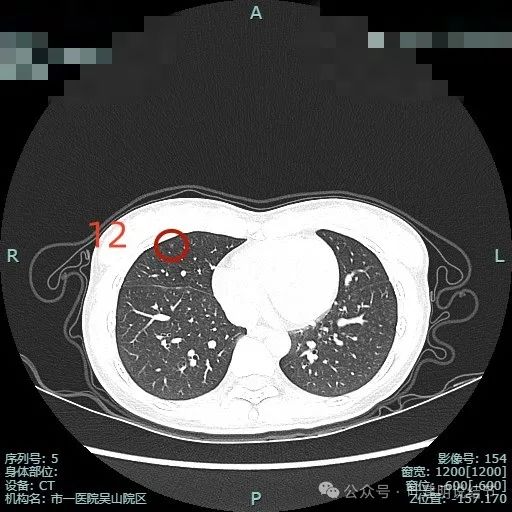

病灶12:右中叶微小淡磨玻璃结节,整体轮廓较清,考虑肺泡上皮增生可能。